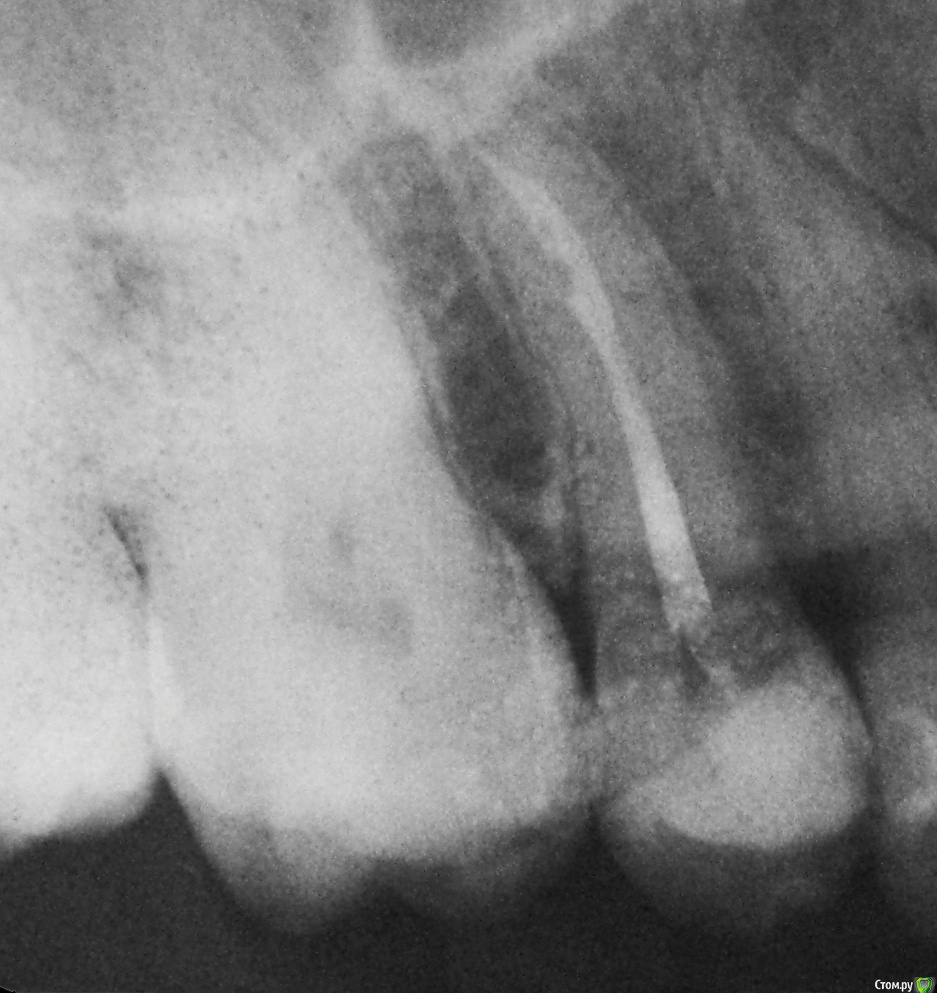

Валентина85 Опубликовано 5 марта, 2015 Автор Поделиться Опубликовано 5 марта, 2015 Гарриевич, большое спасибо, что уделяете внимание моей проблеме. К врачу обращалась. Несколько дней назад. На счет десны между 5 и 6 смотрел только визуально, сказал что выглядит все норм. На счет того что, сильнее зуб реагирует при постукивании именно по передней поверхности я тогда так конкретно не говорила (это я поняла только вчера, когда уже самостоятельно простучала зуб со всех сторон перед написанием сообщения на форуме ), жалобы были просто на то, что больно при постукивании вообще. Постучал по зубам: когда было больно, когда нет. Доктор говорит, что по снимку корневой канал запломбирован хорошо, смысла перелечивать зуб не видит. Причину этих симптомов объясняет просто повышенной чувствительностью на саму процедуру лечения. Говорит, что со временем это должно пройти. На сегодняшний день прошло уже почти 1,5 месяца после лечения. Никакой положительной динамики не наблюдается. В связи этим требуется альтернативное мнение специалистов с этого форума. Спасибо. Ссылка на комментарий

Валентина85 Опубликовано 5 марта, 2015 Автор Поделиться Опубликовано 5 марта, 2015 Снимка нет Зуб был 8 лет назад пролечен по кариесу, был живой. Под пломбой случился вторичный кариес. Сначала просто пролечили по обратимому пульпиту, заменили пломбу, не депульпировали в надежде что организм справиться. Но зуб стал болеть сразу после лечения, тогда уже депульпировали и в то же посещение сразу запломбировали каналы постоянным материалом - гуттаперчей. В процессе лечения доктор сказал, что немного кровило, но некритично. Сказал что у зуба 1 прямой канал, что никаких латералей мануально и по снимку не обнаружил, что случай не сложный. Работали с коффердамом, промывали гипохроритом, был апекс-локатор и самоадаптирующиеся файлы - все по последней моде Ссылка на комментарий

Гарриевич Опубликовано 5 марта, 2015 Поделиться Опубликовано 5 марта, 2015 1 Не считаю. По снимку все смотрится прилично и даже при самой плохой работе без коффердама и прочего, герметизм пломбы за 2 месяца не рухнет2 Может и само пройти, мы человеки - народ странный 3 в любом случае согласовывайте действия с Вашим лечащим врачом, а пародонтолог у него в клинике я думаю найдется Ссылка на комментарий

Гарриевич Опубликовано 6 марта, 2015 Поделиться Опубликовано 6 марта, 2015 Или Вы считаете что там нет инфекции вообще? Почему тогда зуб уже 1,5 месяца болит при постукивании?Судя по Вашему описанию работы доктора, могу считать, что там вообще нет инфекции внутри зуба и она туда не попадает изза герметичной пломбы. То, что болезненно у Вас постукивание именно сбоку, со стороны щеки или неба, говорит в пользу пародонта. Поэтому и рекомендовал Вам его Ссылка на комментарий